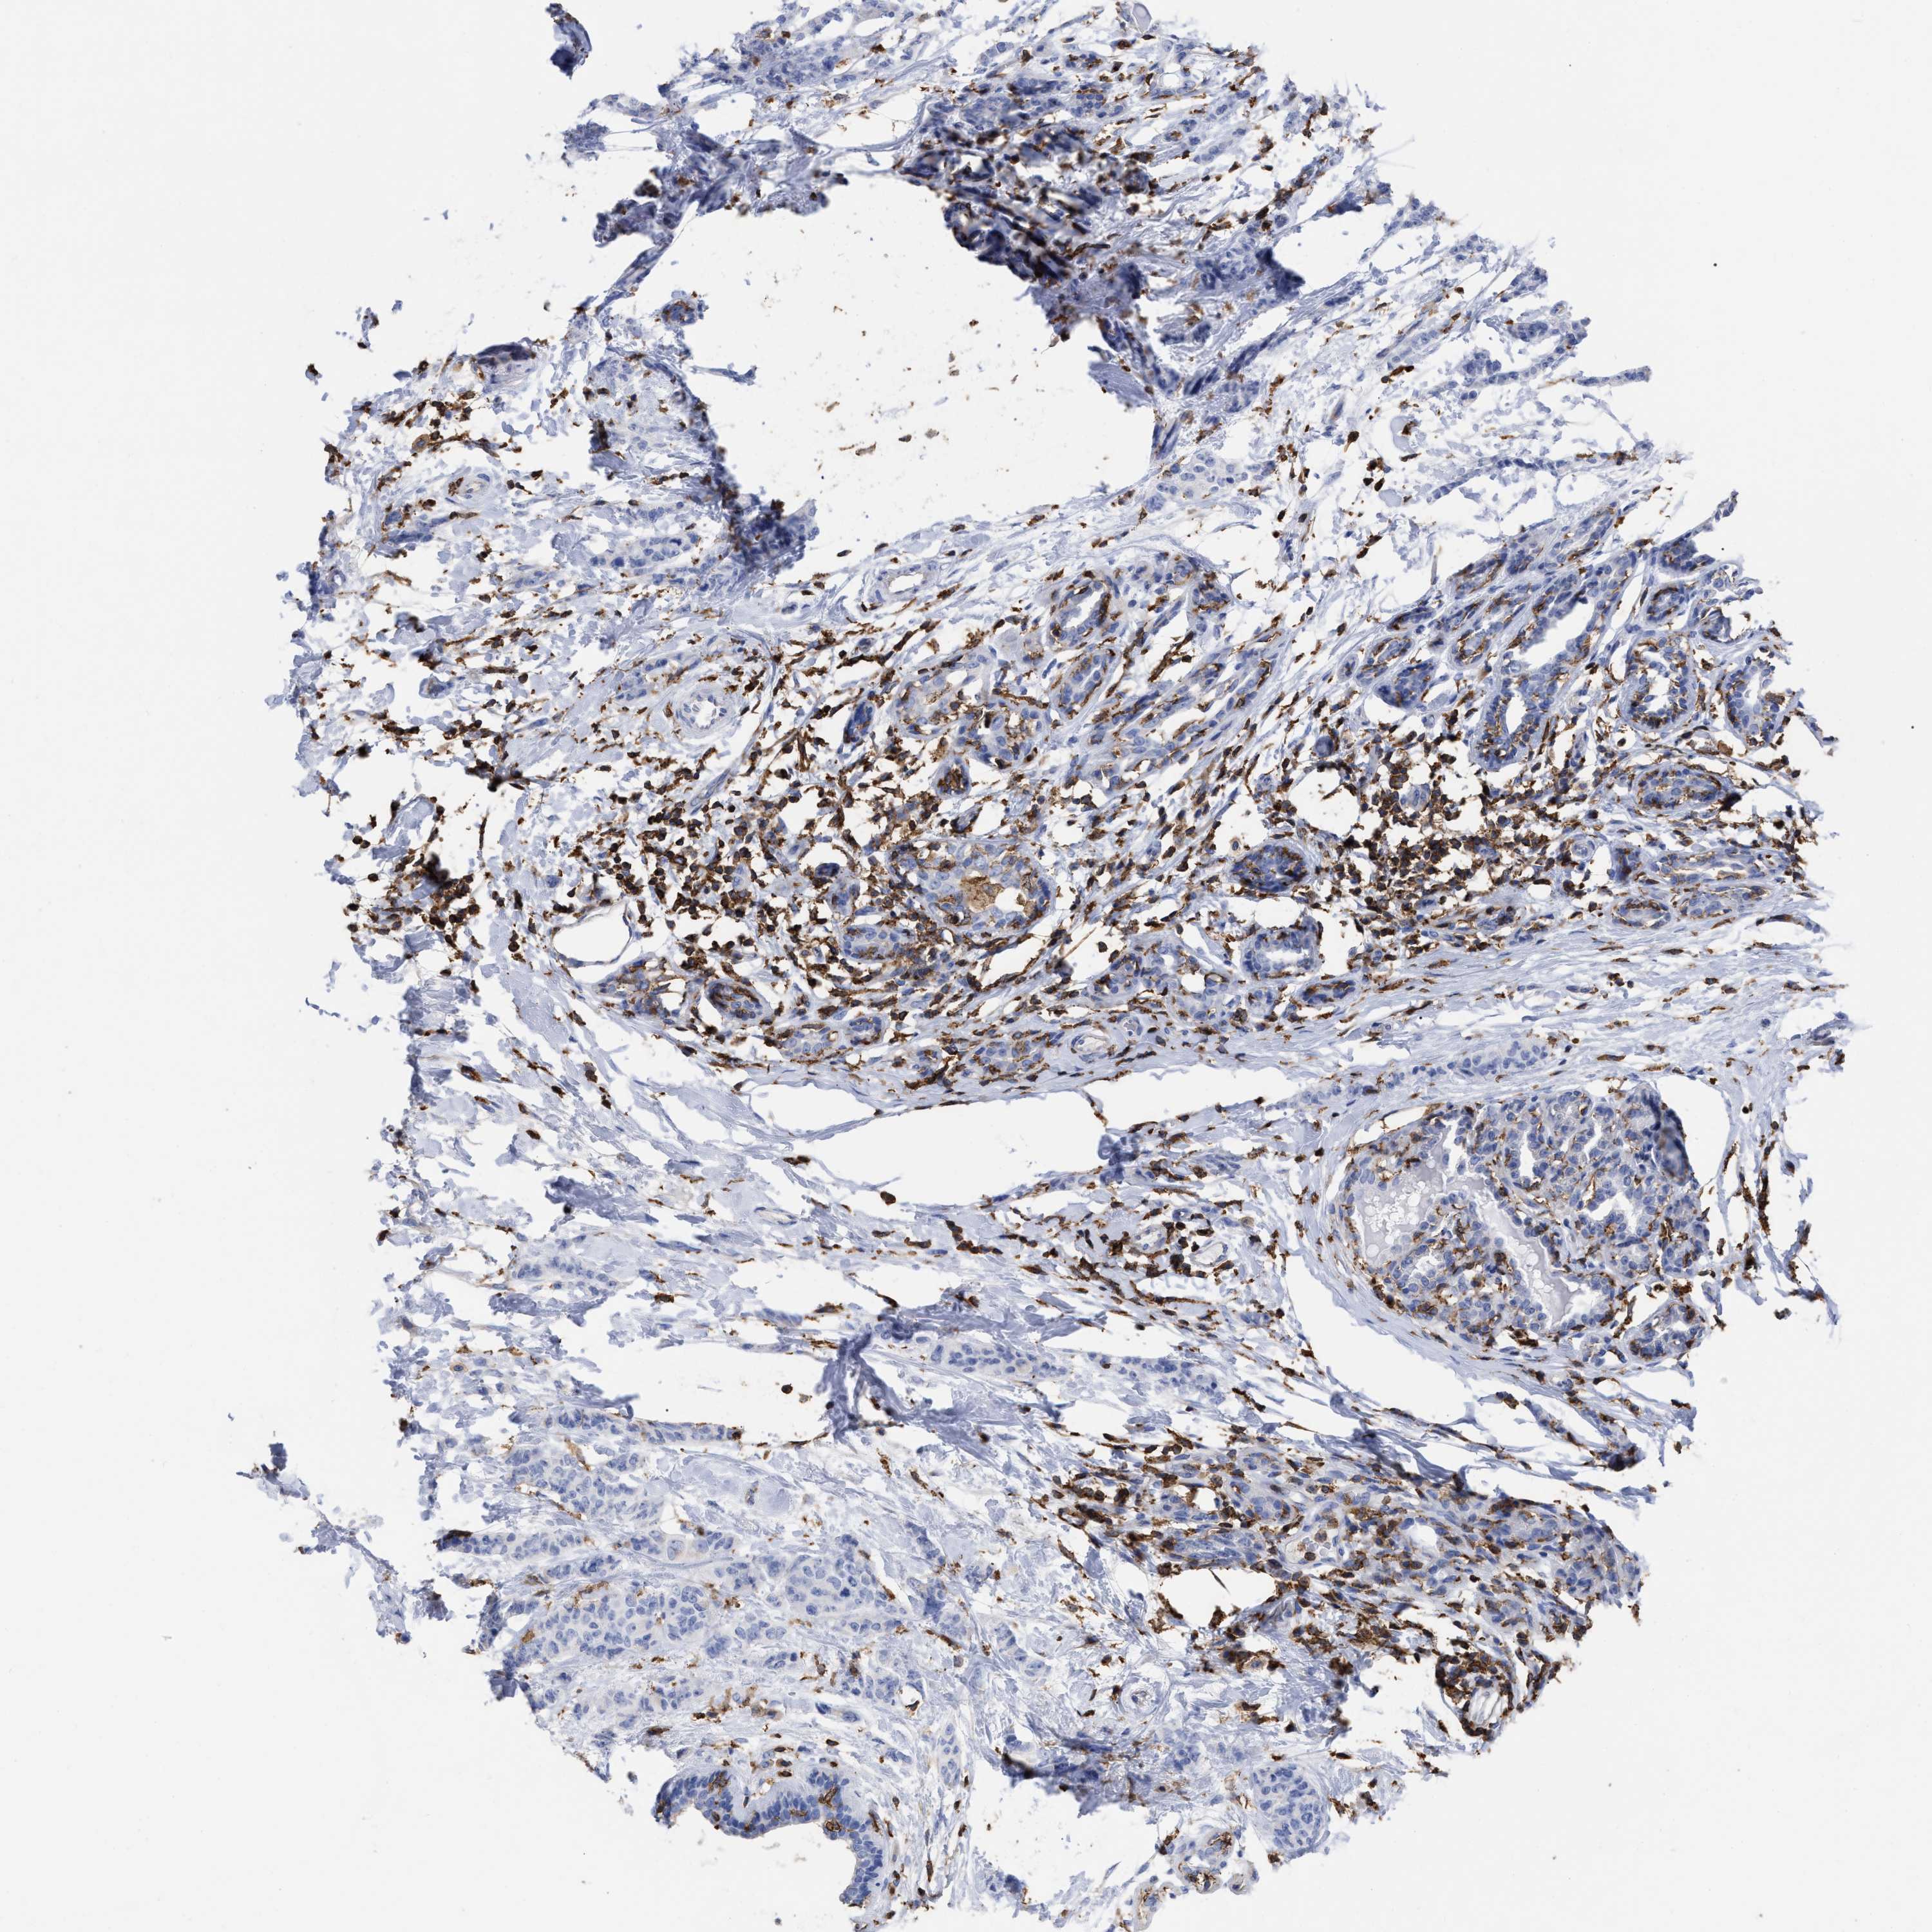

CANCER BREAST CANCER Show tissue menu

BRCA TCGA BRCA VALIDATION PROTEIN EXPRESSION